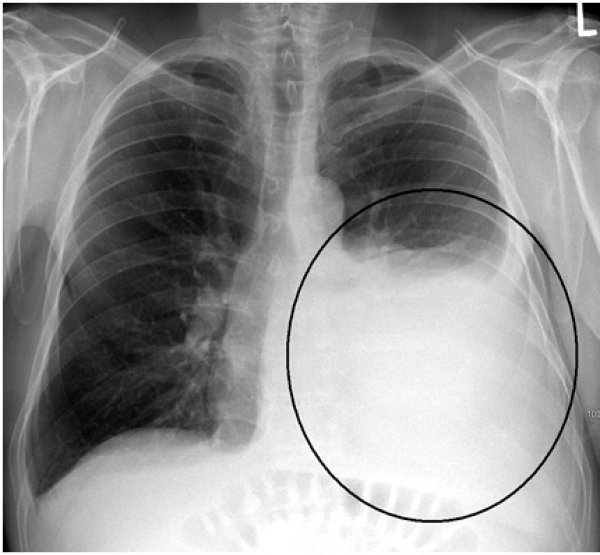

Ljubica Gašić iz Beograda očekivala je da će lako proći zakazanu kontrolu kod ljekara. Međutim, rezultati su bili poražavajući. Pronašli su joj rak pluća, u šezdeset petoj godini. Karcinom je zahvatio desno plućno krilo i ljekari su joj rekli da ne mogu da je operišu.

- Kod ljekara sam otišla samo da podignem lijekove za srce. Iskoristila sam to i požalila sam se na malaksalost, koju sam osjećala par dana ranije. Nakon prvog slušanja pluća, doktorki se nje dopalo šta čuje, zbog čega me je poslala kod specijaliste. Nakon desetak dana odlazim kod plućnog ljekara. Tada sam se već osjećala dobro i dok sam čekala da uđem u ordinaciju zapitala sam se šta ću ja ovdje. Ipak, snimak je pokazao da imam rak pluća, koji nije mogao da se operiše - priča Ljubica za "Blic".

U većini slučajeva, rak pluća ne daje nikakve simptome sve dok bolest već ne uznapreduje. Ipak, postoji i mnogo slučajeva u kojima ljudi simptome ove teške bolesti zamjenjuju nečim drugim, što je uvijek fatalna greška.